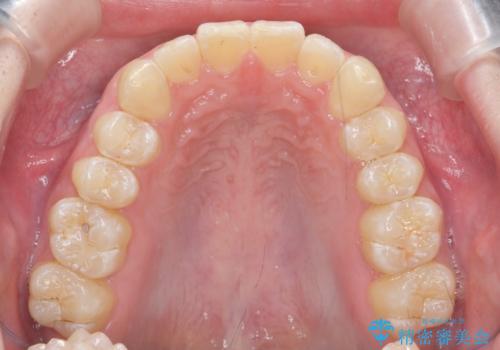

クロスバイト・歯並びが原因の歯肉退縮歯、矯正治療による審美性の改善

- 前歯の歯並び、下顎前歯の歯ぐきの下がり(歯肉退縮)の改善を求めて来院されました。

歯肉退縮の根本的な原因はすれ違った噛み合わせによる為害性のある咬合状態にあるため、歯肉退縮に対し結合組織の移植術を行うのではなく当該歯を抜去し部分矯正を含めた治療計画を立案します。

矯正治療を行ったことで、噛み合わせが安定し審美性も機能性も向上することができました。